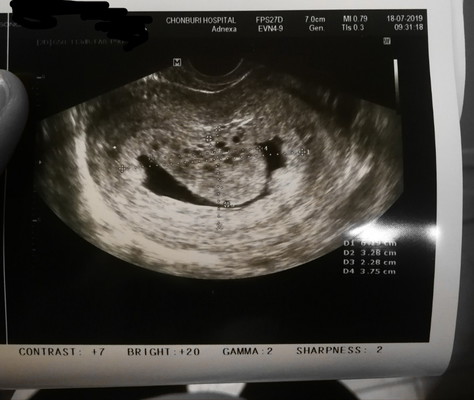

แชร์ประสบการณ์ ครรภ์ไข่ปลาอุก

แวะมาแชร์ประสบการค่ะ เรื่องครรภ์ไข่ปลาอุก เราเป็นคนหนึ่งที่เข้าข่ายมีบุตรยาก เพราะประจำเดือนมาไม่ปกติ มีภาวะไข่ไม่ตกเรื้อรัง (PCOS)เราปรึกษาหมอ รพ.รัฐบาล คุณหมอก็ให้ตรวจเลืิิอด ตรวจอสุจิสามี ปกติทุกอย่าง แล้วหมอสั่งยากระตุ้นการตกไข่ให้ 1 แผง ........ หลังจากนั้นก็ท้องค่ะ 5 week ไปซาวด์ รพ. เจอถุงครรภ์ 6 week ไปซาวด์ที่คลีนิค เจอถุงครรภ์ไม่เจอหัวใจเด็ก 8 week ไปซาวด์ที่คลีนิค ถุงครรภ์เริ่มรูปร่างแปลกๆ หมอบอกท้องลม นัดไปเช็คที่ รพ.อีกที่เพราะสิทธิ์การรักษาอยู่ รพ. 9 week 5 day ซาวด์ผ่านช่องคลอดที่ รพ. หมอสรุปว่า"ท้องไข่ปลาอุก" พบได้ 1-3คน/คนท้อง 1000 คน ........ ลักษณะไข่ปลาอุกคือมีก้อนเนื้องอกขึ้นมาบริเวณถุงครรภ์แต่ไม่มีตัวเด็ก ก้อนเนื้อโตขึ้อย่างรวดเร็ว หมอสั่งแอดมิดและขูดมดลูกทันที ก้อนเนื้อมีโอกาสเป็นมะเร็งเนื้อรก ........ สาเหตุ : ยังไม่มีความจัดเจนว่าเกิดจากอะไร แต่คาดว่าไข่ที่ตกไม่มีคุณภาพ จึงทำให้การปฏิสนธิไม่สมบูรณ์ ......... พักรักษาตัว พักท้อง 1 ปี ค่อยวางแผนกันใหม่จร้า ✌️ปล.เป็นกำลังใจให้แม่ๆทุกคนสมหวังในการตั้งครรภ์นะคะ